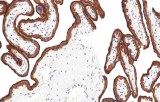

A tiroglobulina é amplamente utilizada como marcador de epitélio folicular tiroideu diferenciado e é útil para apoiar a origem tiroideia em lesões primárias e metastáticas. A expressão pode estar reduzida, focal ou ausente em carcinomas tiroideus pouco diferenciados ou desdiferenciados; a interpretação deve considerar possíveis limitações técnicas e contextuais.

PAX8 é um fator de transcrição nuclear expresso em células foliculares da tiroide e é útil para apoiar a linhagem tiroideia, particularmente em tumores com expressão diminuída ou ausente de tiroglobulina. A interpretação requer consciência de que a expressão de PAX8 não é específica do tecido tiroideu e pode ser observada em neoplasias epiteliais não tiroideias selecionadas.

A calcitonina é o marcador imunohistoquímico principal de diferenciação de células C parafoliculares e central para o diagnóstico de carcinoma medular da tiroide na maioria dos casos. Embora mostre alta utilidade diagnóstica em cenários primários e metastáticos típicos, foram relatados tumores calcitonina-negativos raros; os resultados devem ser sempre interpretados em conjunto com morfologia, achados clínicos e estudos complementares quando indicado.

A galectina-3 é um dos marcadores imunohistoquímicos mais estudados em patologia tiroideia e é expressa com maior frequência em tumores malignos derivados de folículos do que em nódulos benignos. No entanto, a expressão também pode ser observada em certas condições tiroideias benignas ou inflamatórias. O seu valor diagnóstico é portanto maior quando utilizado como parte de um painel imunohistoquímico multiparamétrico em vez de como marcador isolado.

A hormona paratiroideia é um marcador chave para confirmação da origem paratiroideia e particularmente útil no diagnóstico diferencial entre lesões paratiroideias e tiroideias com características histológicas sobrepostas. Apoia a confirmação de linhagem em adenomas paratiroideus, carcinomas e tecido paratiroideu ectópico ou intratiroideu; a interpretação é feita em correlação com morfologia e achados clínicos.